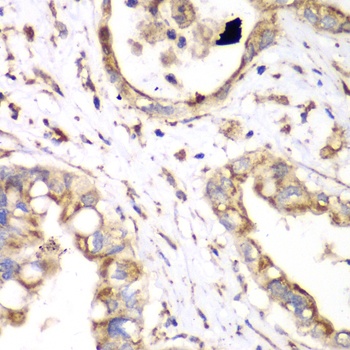

IHC analysis of HADH using anti-HADH antibody. HADH was detected in a paraffin-embedded section of human pancreas ductal adenocarcinoma tissue. Heat mediated antigen retrieval was performed in EDTA buffer (pH8.0, epitope retrieval solution). The tissue section was blocked with 10% goat serum. The tissue section was then incubated with 2 µg/ml rabbit anti-HADH Antibody overnight at 4°C. Peroxidase Conjugated Goat Anti-rabbit IgG was used as secondary antibody and incubated for 30 minutes at 37°C. The tissue section was developed using HRP Conjugated Rabbit IgG Super Vision Assay Kit with DAB as the chromogen.